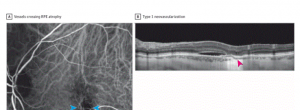

Direct Visualization of a New Choroidal Vessel...

Direct Visualization of a New Choroidal Vessel on Spectral-Domain Optical Coherence Tomography